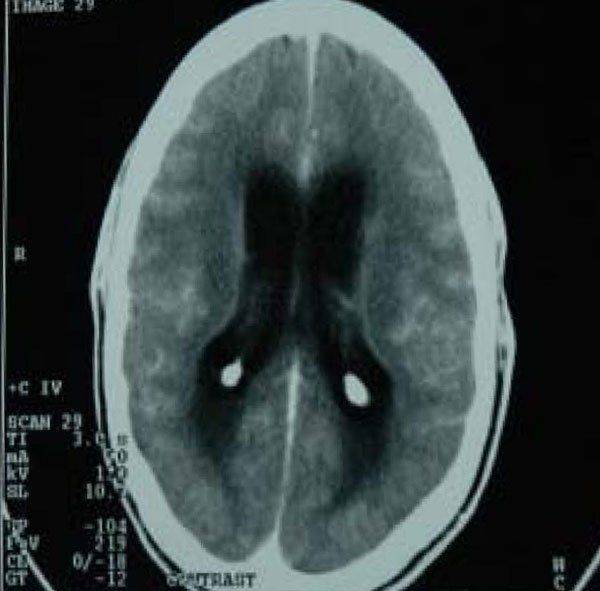

Из-за схожести симптомов с поражениями головного мозга другой природы необходима тщательная дифференциальная диагностика. Сначала изучается анамнез пациента и выясняются причины туберкулёза. Проводятся лабораторные анализы крови, мочи, мокроты и других жидкостей для выявления микобактерий. Для точного определения поражения головного мозга микобактериями выполняется пункция ликвора.

Чтобы установить стадию болезни, область и степень поражения, проводят рентгенографию и ультразвуковые исследования. При возникновении сомнений в диагнозе могут быть назначены КТ или МРТ.